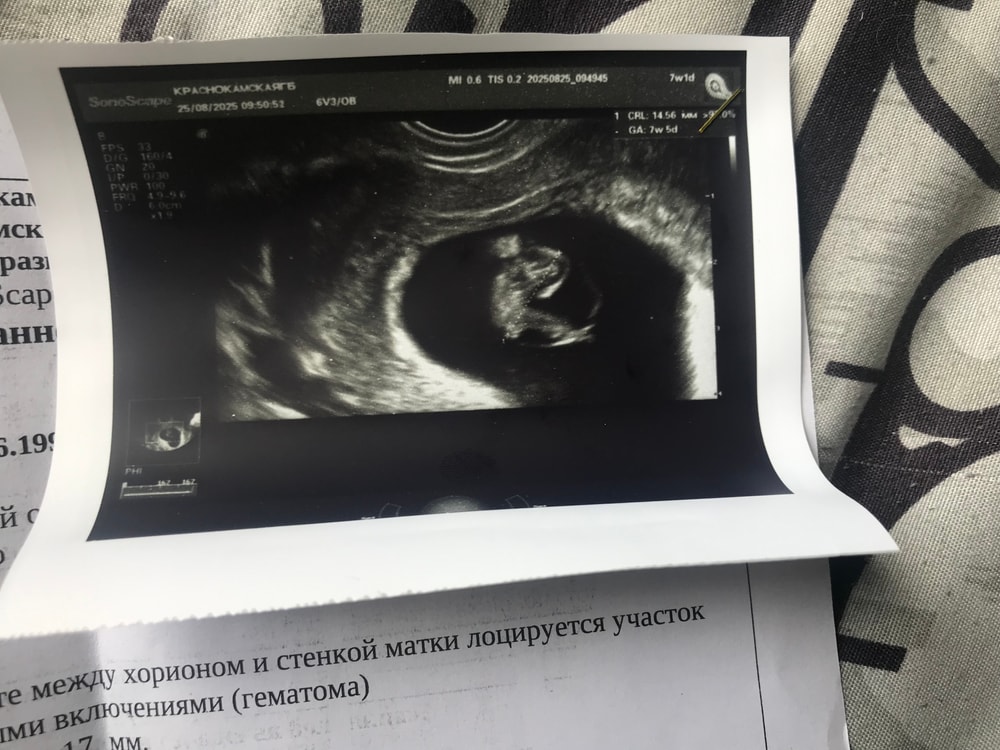

Нет не критично, конечно то, что гематома больше размера пя это риски выкидыша. Вам транексам назначали? Пока у вас ситуация требующая наблюдением за гематомой в остальном беременность прогрессирует СБ есть.

Alina, у вас гематома если правильно поняла боковое расположение. точнее нижний сегмент. Такое расположение легче уходит в регресс нежели если бы было над пя или снизу пя( выделения?!). Все будет хорошо. Постельный режим и консультация врача по сохраняющей терапии. Увеличить поддержку прогестероном. Если отменили эстрогены вернуть прежнюю дозу . И транексам но это выпишет врач. Обычно пьют при выделениях и гематоме от 250/3 раза если красные выделения разово 1500. И дальше в течении 5 дней. Но повторюсь нужен врач. Ваш сохранять не планирует нужен другой врач. Возьмите консультацию репродуктолога онлайн много где это бесплатно по акции.

Не критично, но гематому надо наблюдать. Вам должны назначить лечение.

В Нижнем сегменте у вас гематома? Если в Нижнем то она должна давать выделения.? У вас есть признаки?